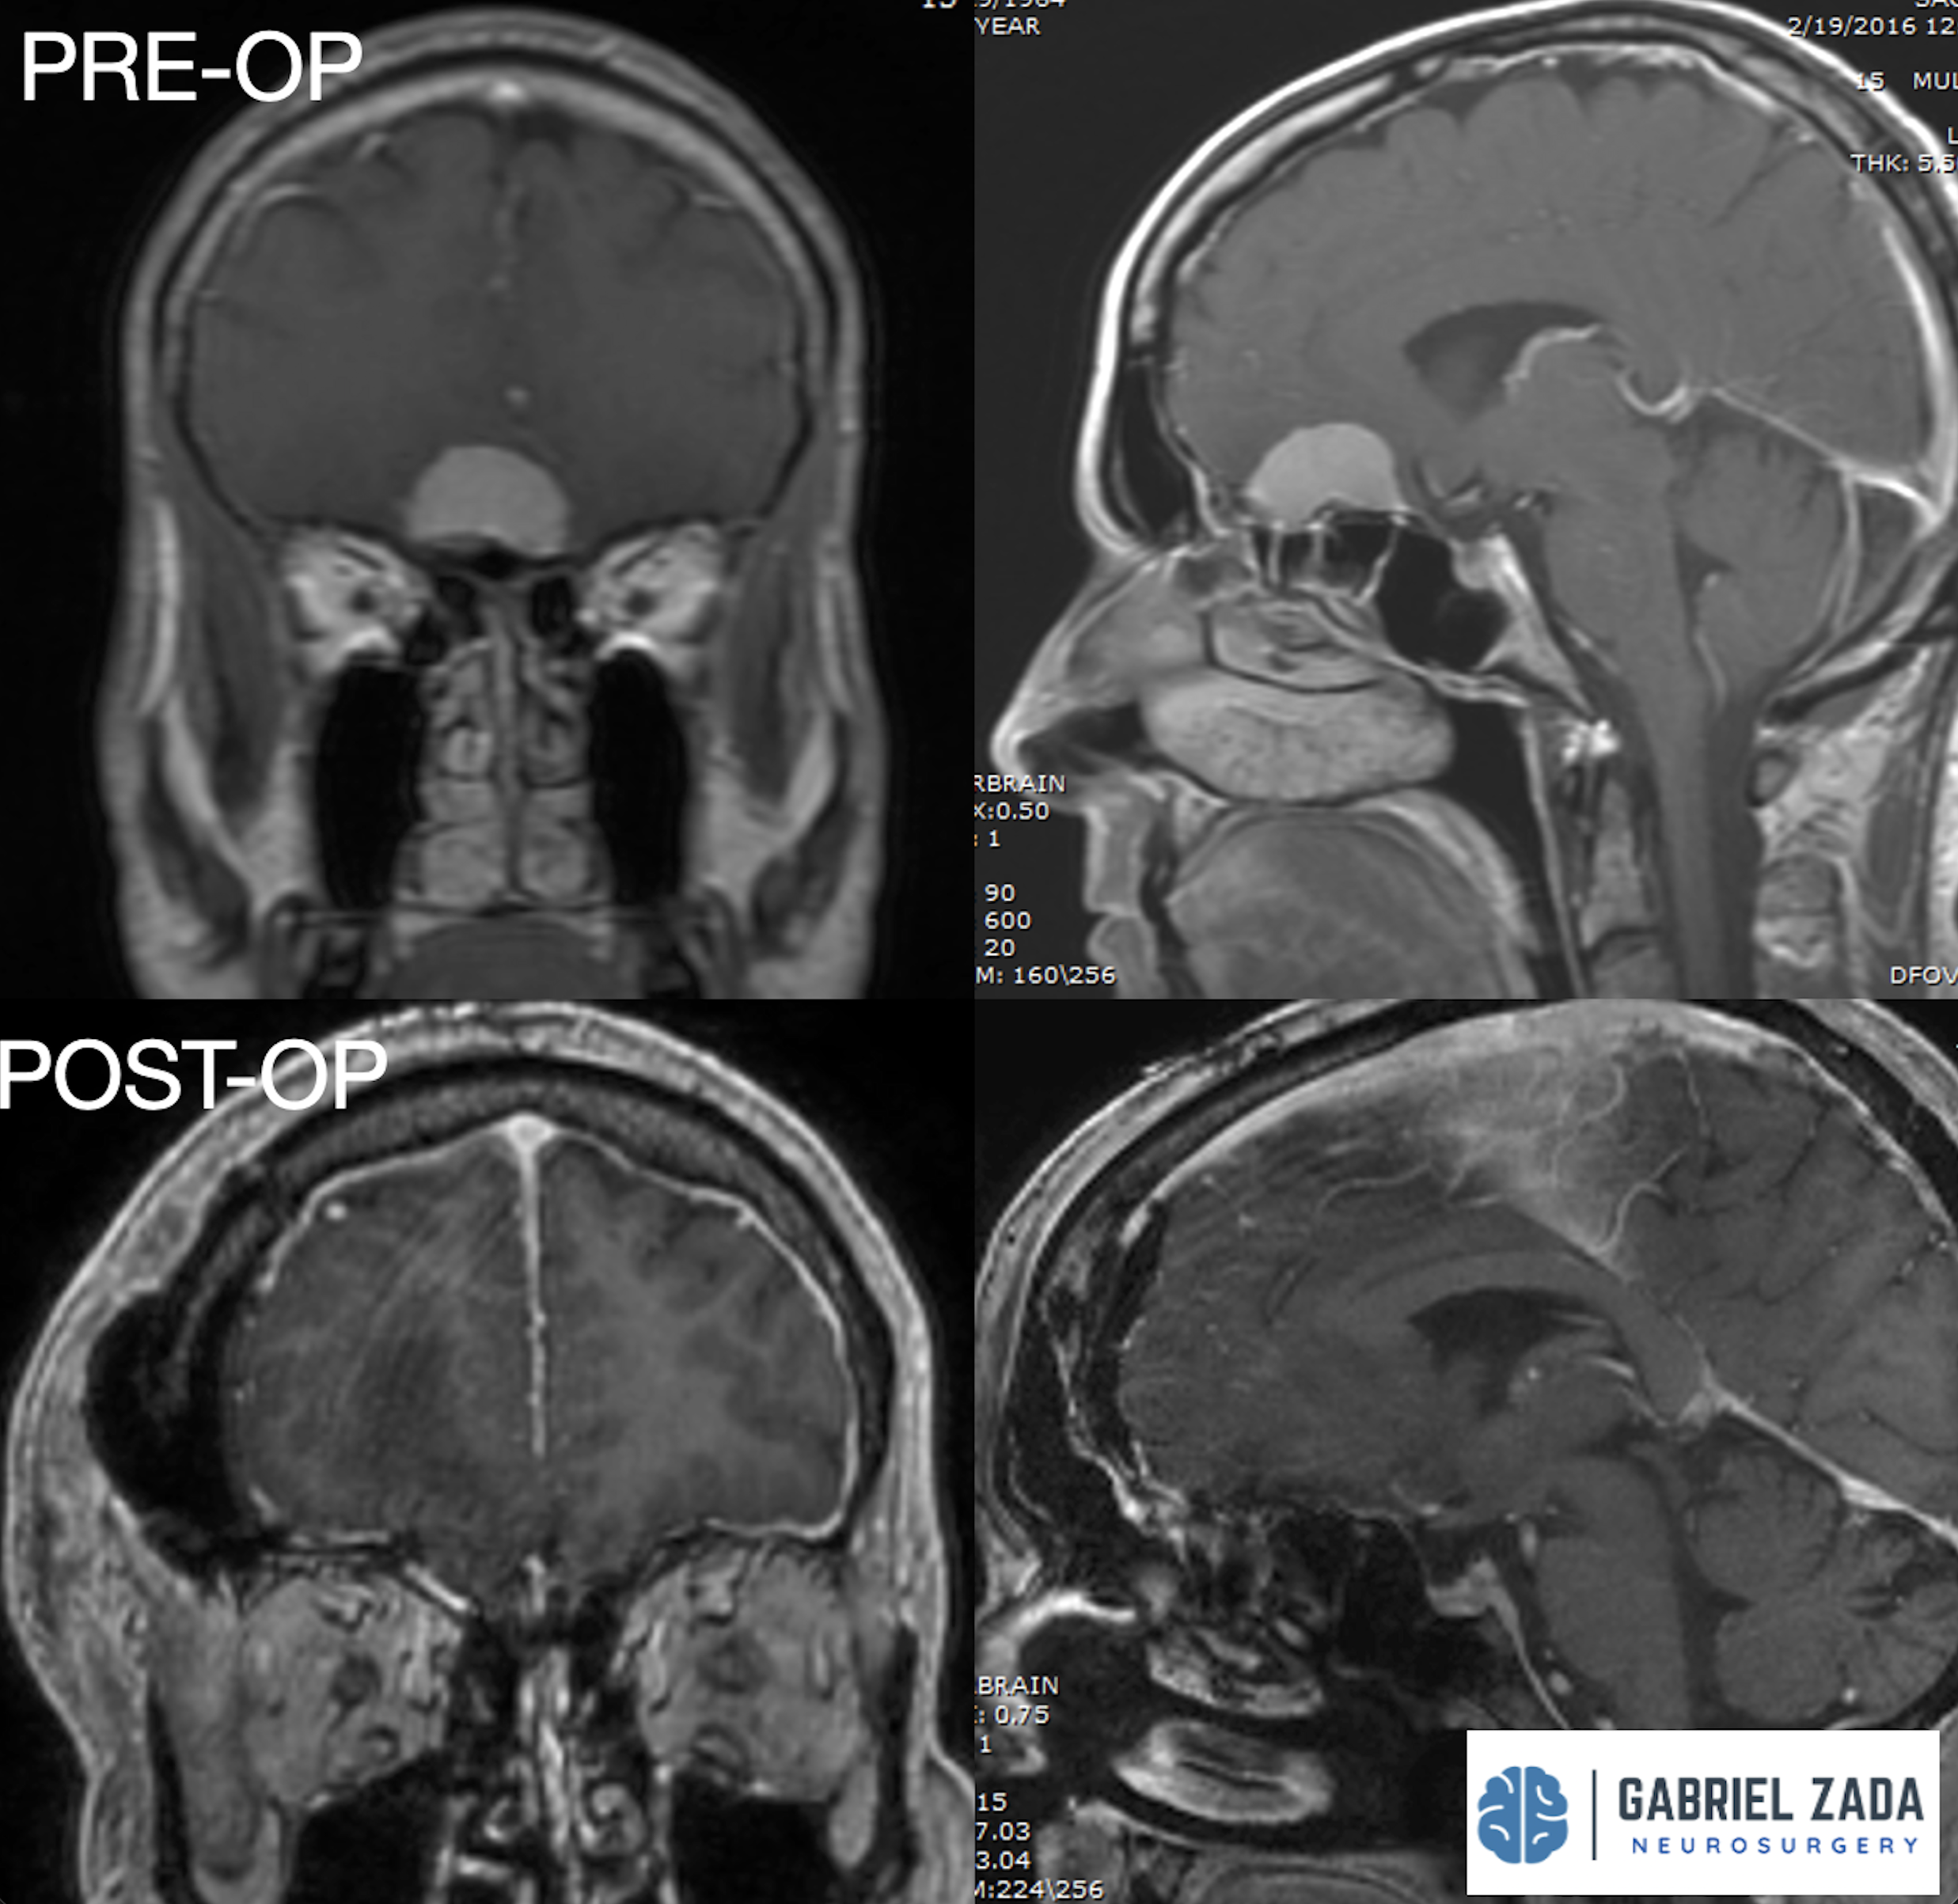

Explore this comprehensive gallery featuring pre‑ and post‑operative imaging of patients with skull‑base tumors treated by Gabriel Zada, MD, MS, FAANS, FACS. These cases highlight Dr. Zada’s expertise in advanced neurosurgical techniques and outcomes.

*Representative cases shown for educational purposes. All images de-identified. Individual results vary.